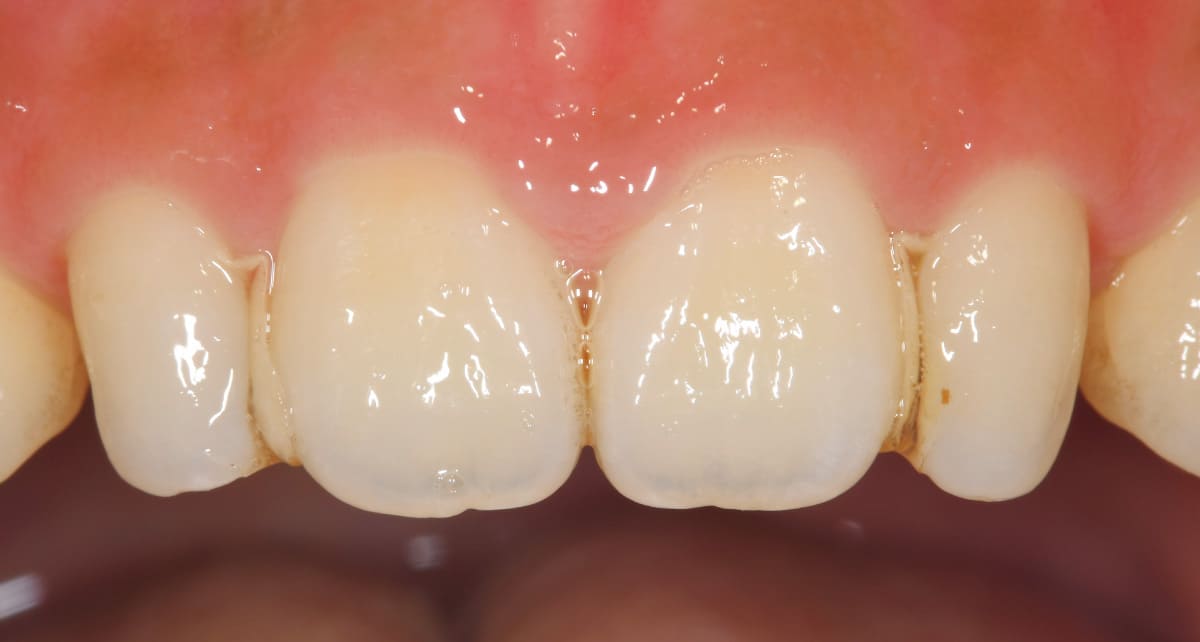

ラミネートベニア|イメージはネイルチップ。前歯のトラブルを改善。

Before

After

歯の表面のエナメル質を薄く削り、薄い板状のセラミックを直接貼り付ける治療法。歯の色や形、すきっ歯などの改善に対応する。いわゆる付け爪のイメージで治療は短期間、歯への負担も少ない。前歯の処置に用いられることが多い。

【料金】10万円〜

【治療期間】1週間〜3週間程度